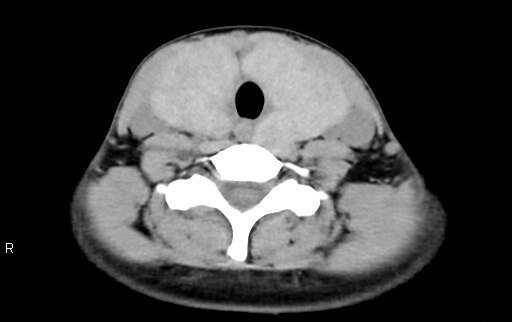

当院では、CTAや金属アーチファクトの低減、また甲状腺の容量測定のオーダーが出た場合にDual Energyにて撮影をしています。特に甲状腺の容量測定時は低keV画像を利用して容量測定を行っています。

下記症例は19歳女性、甲状腺摘出術前で甲状腺容量測定の依頼があり、従来のCT装置では、Dual Energy撮影が出来なかったため、管電圧120kVで撮影していましたが、甲状腺の辺縁が同定しにくく、辺縁をトレースするのに苦労していました。Revolution CTが導入され、Dual Energy撮影が可能となり、低keVの画像を使用することで、甲状腺のCT値が上昇し境界が明瞭になり、容量測定が容易になりました。

40keV